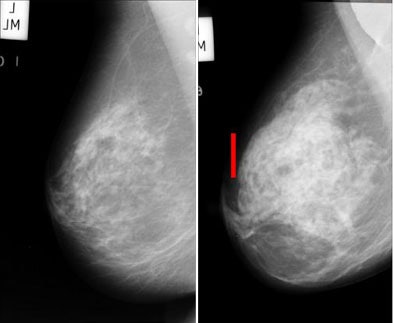

![]() |

| Architectural distortion in breast tissue (seen in mammographic breast image at right) is a potential indication of malignancy that is often missed by radiologists and CAD systems alike. The distortions can be difficult to appreciate even in the enlarged view (bottom). Images courtesy of Rangaraj Rangayyan, Ph.D. |

The most common form of architectural distortion is represented by spiculations arising from a point, Rangayyan said. The second most common form is a focal retraction at the edge of the parenchyma, where tissue strands are pulled, forming a gull wing pattern. In the third type, the incipient mass, tissue components are pushed out.